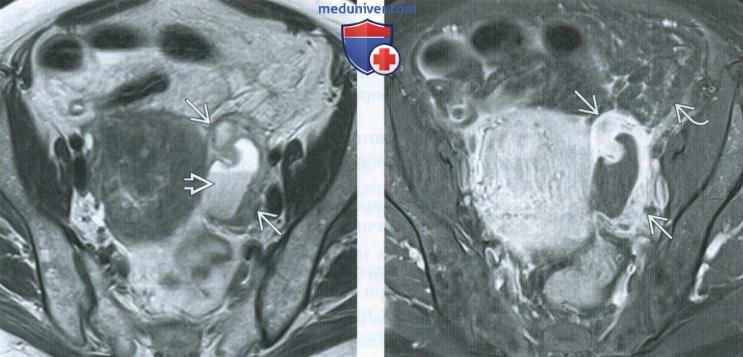

КТ диагностика тубоовариального абсцесса: Подходы и изображения

Раздел: Объективный взгляд